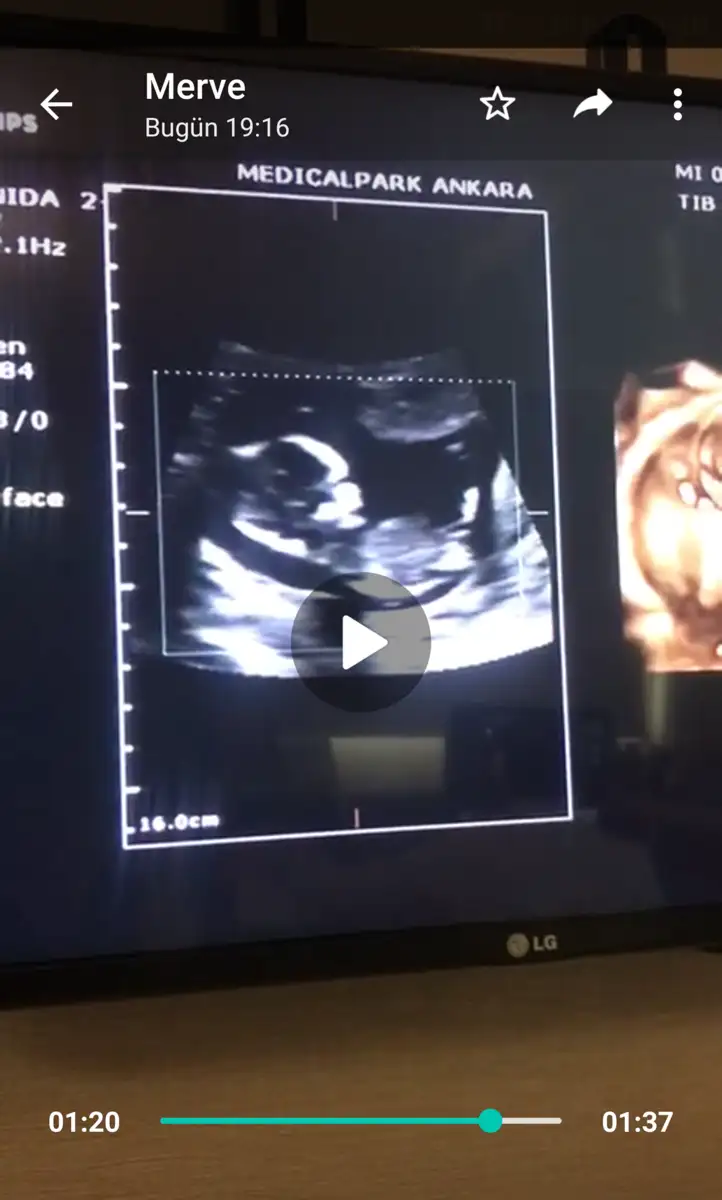

8 haftalık görüntü tahmin alabilirmiyim

Eklentiler

• 5DF6B3C7-374F-4E15-913C-1AB0BFEC0082.webp

5DF6B3C7-374F-4E15-913C-1AB0BFEC0082.webp

12,9 KB · Görüntüleme: 95

Merhabalar. Beş haftalıkken yuvarlak bir kesenin tam solundaydı ama 7 haftalıkken görüntü böyle ortada çıktı. Cinsiyet tahmini yapılabilir mi bundan da?

• 00A39E87-DFC6-4B87-A8CD-CE4AC30E65B5.webp

00A39E87-DFC6-4B87-A8CD-CE4AC30E65B5.webp

66,8 KB · Görüntüleme: 96